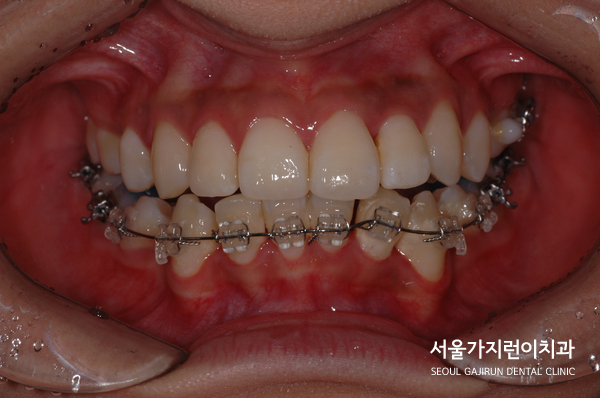

환자분의 경우 상악앞니가 많이 돌출된 케이스에 하악 앞니가 안쪽으로 기울어져 있는 상태였는데요. 전체적으로 치열이 많이 비뚤어져 있었기 때문에 앞니로 음식을 끊어먹는 것에 어려움을 겪고 계셨습니다. 특히 입을 다물려 해도 앞니의 돌출감 때문에 잘 다물어지지 않았고 중심선도 맞지 않아 여러 불편함을 안고 계셨는데요.

상악앞니의 돌출감이 심했기 때문에 상악의 경우 설측교정장치를 이용하고 하악의 경우 순측으로 진행하는 콤비교정을 진행했습니다. 돌출입 교정시에 이미 튀어나온 입에 튀어나오는 장치를 착용할 경우 교정기간 내내 입이 더 튀어나와보이는 증상으로 스트레스를 호소할 수 있었는데요. 이렇게 설측으로 진행하고 콤비교정으로 진행하면 합리적으로 치아교정을 마무리할 수 있습니다.

환자분의 경우 충분한 치아이동 공간이 필요했기 때문에 상하악 발치를 모두 진행하였으며 씹는 면을 맞게 조정하고 발치공간을 닫아나가는 시간이 필요했는데요. 2년 정도 소요된 이후에 돌출감이 사라지고 치아들이 제 자리를 찾아간 것을 확인할 수 있었습니다.

환자분이 진행한 치아교정은 설측탄댐교정방식이었는데요. 치아의 쓰러짐 없이 안정적으로 자리를 찾았고 미니스크류를 더해 정교한 컨트롤이 진행되었습니다. 사진을 보면 중심선도 맞고 뻐드러진 돌출감도 많이 해소되었는데요. 전체적인 치열이 잘 정돈된 것을 확인할 수 있었습니다.